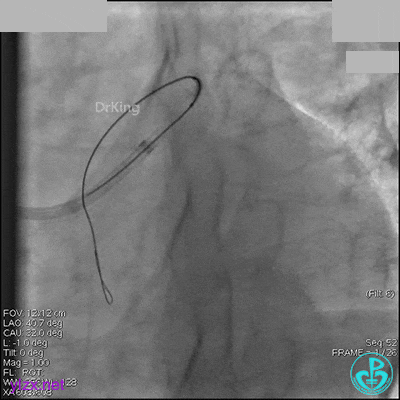

右冠脉中段充分扩张后欲植入3.5×38mm支架时,支架难以通过中远段扭曲处,且指引导管、导丝弹出飞扬。反复尝试导丝重新到达右冠脉远端时通过不顺利,局部造影剂滞留,远端血流接近3级。

右冠脉血流3级,患者无症状,终止手术。

1周后再次上台,右冠脉3级血流,3段局限性严重狭窄,内膜模糊,应该是上次操作夹层遗留下的血肿。